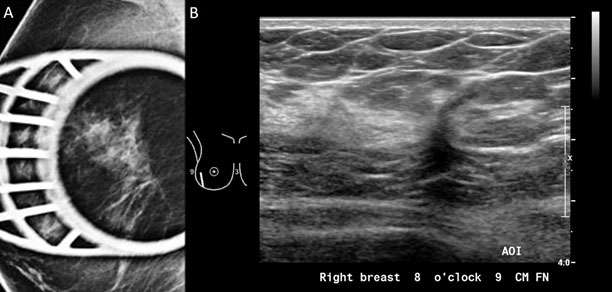

Figure 6: A) Spiculated mass was visualized in the right breast with spot compression view on mammogram. B) Sonographic evaluation of the right breast was performed in the region of the mammographic finding. At the 8:00 position 9 cm from the nipple, there is an irregular hypoechoic solid mass with indistinct margins oriented antiparallel to the chest wall demonstrating posterior shadowing, BI-RADS Category: 4C suspicious finding. Pathology confirmed invasive ductal carcinoma, Grade 1.